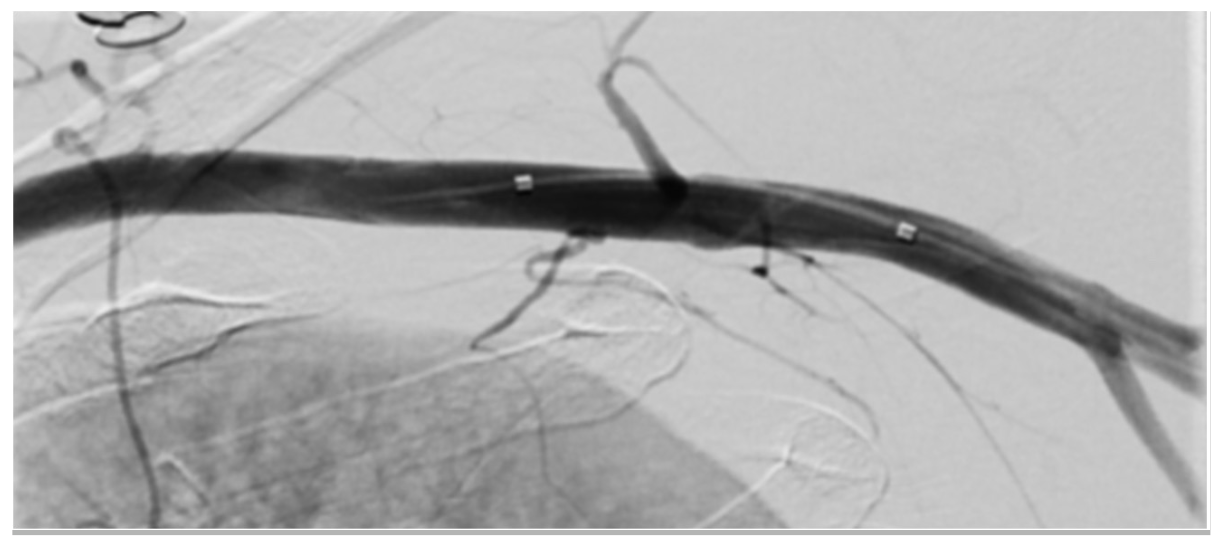

There was still persistent oozing, possibly due to subcutaneous position of the suture knots. We then advanced a 10-cm, 7-Fr hydrophilic braided Arrow sheath (Teleflex) to avoid kinking and inserted a 6-Fr Angio-Seal directly into the sheath (Figure 7 and Figure 8). There was sufficient length to deliver the footplate into the vessel (Figure 9). Careful traction was applied to the Angio-Seal device until it was against the sheath tip. Then, traction to the whole system brought the footplate to the arteriotomy site and subsequently revealed the tamper tube, which was pushed in good alignment on fluoroscopy to tap the collagen plug in place (Figure 10). Final subtracted angiogram from the over-the-wire balloon catheter confirmed good hemostasis (Figure 11).